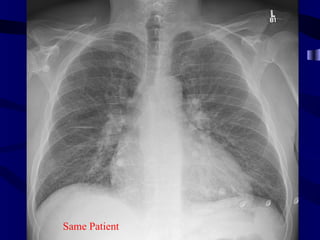

pulmedema

SOB

Same Patient